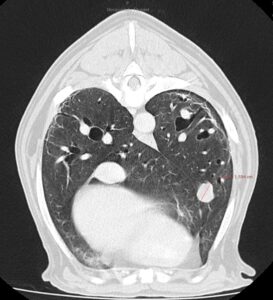

A los 18 meses del diagnóstico, los cuidadores refieren la aparición de hifema y exoftalmia en el ojo derecho, lo que sugiere metástasis, además de una masa perianal compatible con neoplasia indiferenciada (posible melanoma amelanótico). En el estudio de TC se documenta una respuesta completa de la lesión primaria y metástasis nodales y una remisión casi completa de las metástasis pulmonares (lesiones milimétricas equívocas) (imagen 1). Se realiza la resección de la masa perianal, pero los cuidadores rechazan la enucleación.

A los 28 meses se realiza un TC de re-estadiaje antes de considerar el segundo protocolo de radioterapia, donde se documenta una progresión objetiva de la masa oral y ligera progresión de la metástasis pulmonar (imagen 1).